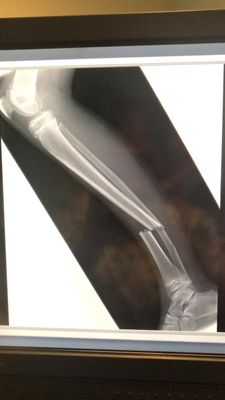

This 12-year-old presented with a short oblique fracture to the right tibia and a segmental fracture to the fibula. Attempts at closed manipulation were unsuccessful.